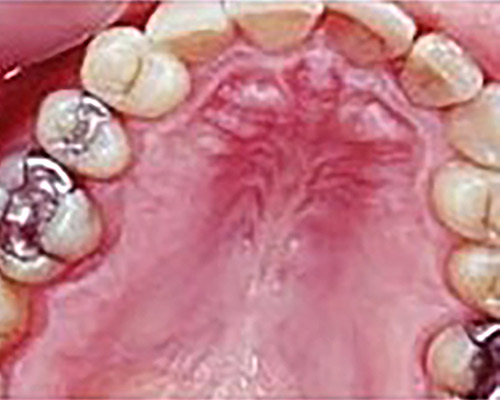

Gentle and painless treatment of dental caries and dental lesions using the most modern techniques and materials from renowned companies with emphasis on aesthetics and functional tooth restoration.

We produce photocomposite, ceramic (inlay, onlay) and amalgam fillings of the latest generations.